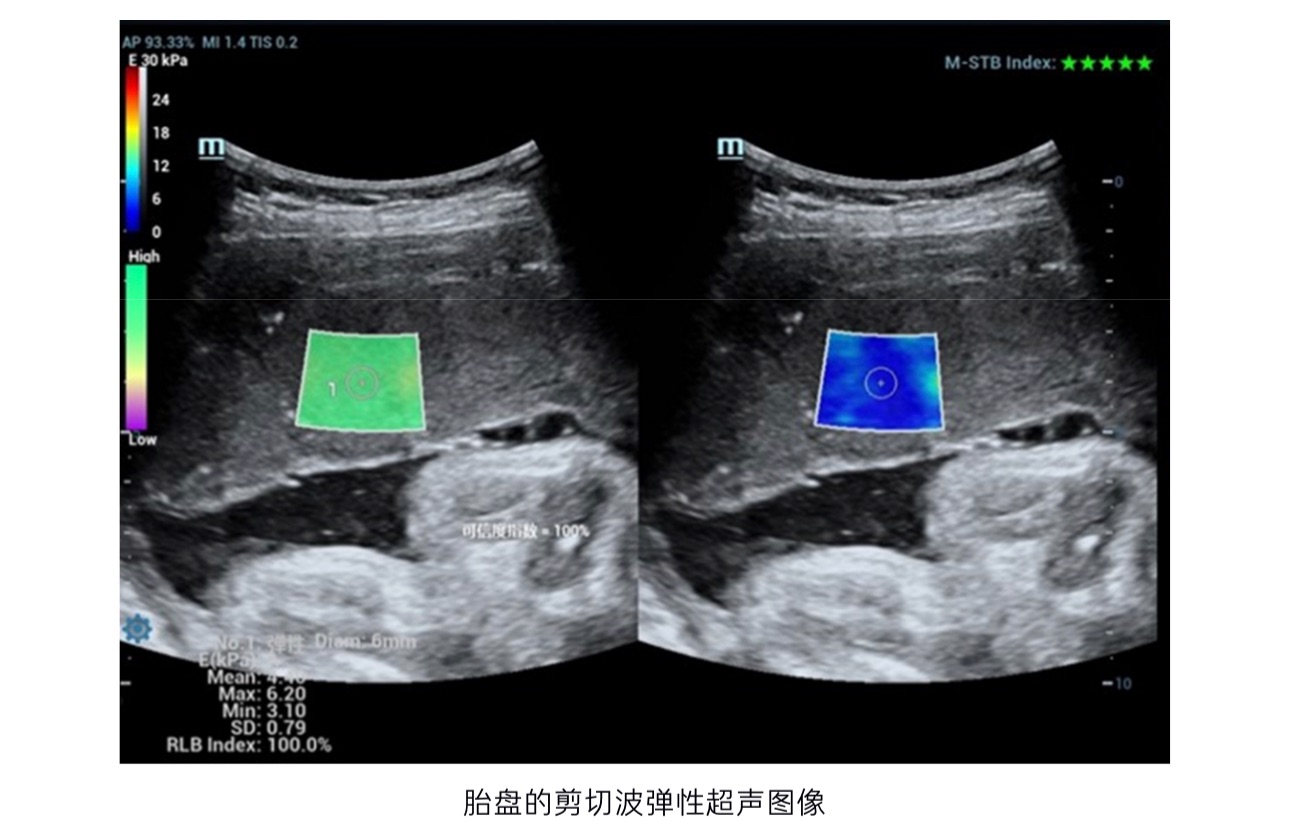

超声弹性成像技术是近年来热门超声技术。从早期的应变式到现在的剪切波,弹性成像技术的革新为精准化超声评估提供了重要的辅助作用。如果我们在身上摸到一个包块,我们会去压一压它,感受一下这个包块的软硬度。弹性超声就是将这样一个过程和结果给直观的呈现出来。早期的应变式弹性成像,就是通过超声医生手持超声探头规律地对病灶及周围组织进行按压,从而获取病灶及组织的硬度,然而这项技术有个无法回避的缺点,它无法对组织硬度进行量化评估,仅能做半定量对比或者定性分析。近些年来发展出的剪切波弹性技术,已经不再需要医生进行主动地对病灶加压,通过不同的发射激励,使得剪切波在相应组织区域内传播,再将这一信息接收返回处理,从而形成可视化的图像与可被读取、量化的数据。该技术开创性地量化组织硬度,操作方便,安全可靠、可重复性好,已被应用在肝脏、乳腺、甲状腺等组织疾病诊断中,尤其是在无创诊断肝纤维化中具有重要作用。近年来,已经有越来越多的学者将其应用在胎盘检测中。多项研究表明,妊娠期高血压、妊娠期糖尿病的孕妇的胎盘硬度要显著高于正常孕妇的胎盘。